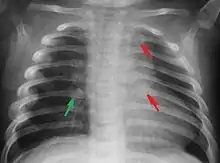

Rib fractures in an infant secondary to child abuse

The immediate physical effects of abuse or neglect can be relatively minor (bruises or cuts) or severe (broken bones, hemorrhage, death). Certain injuries, such as rib fractures or femoral fractures in infants that are not yet walking, may increase suspicion of child physical abuse, although such injuries are only seen in a fraction of children suffering physical abuse.[92][93] Cigarette burns or scald injuries may also prompt evaluation for child physical abuse.[94]